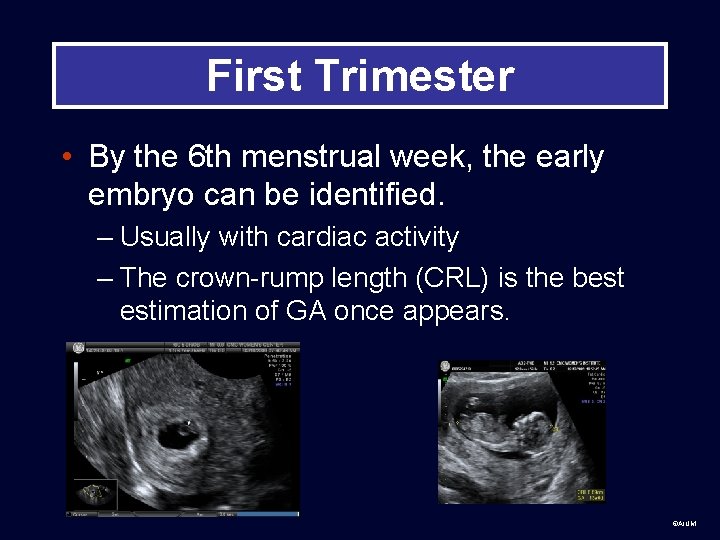

First Trimester • By the 6 th menstrual week, the early embryo can be identified. – Usually with cardiac activity – The crown-rump length (CRL) is the best estimation of GA once appears. ©AIUM